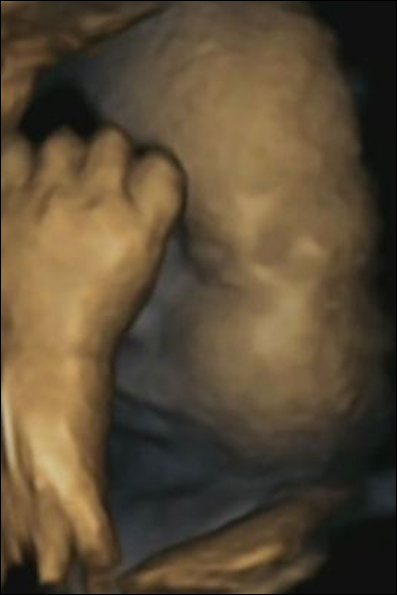

دست کوچکی که به سوی چانه رفته، به طور نگران کننده ای نشان می دهد که این جنین تحت استرس است.

این تصویر قابل توجه، بخشی از مطالعه ای است که نشان می دهد جنین وقتی مادرش عصبی، دچار استرس، تحت فشار و درمانده باشد، صورت خود را لمس می کنند.

محققان معتقدند جنین ها اضطراب مادر را حس کرده و سعی می کنند با قدرت لمس خود این استرس را تسکین دهند.

انسان بالغ و بزرگسال، برای تسکین استرس خود، سر را در میان دستها می گیرد. اما در حالی که ما از هر دو دست استفاده می کنیم، جنین های مادران دچار استرس، ترجیح می دهند فقط از یکی برای لمس کردن صورت استفاده کنند.

اگرچه تحقیقات پیشین نشان داده بود جنین در رحم مادر استرس را متوجه می شود، اما این نخستین تصویری است که این امر را به شکل مستدل نشان می دهد.